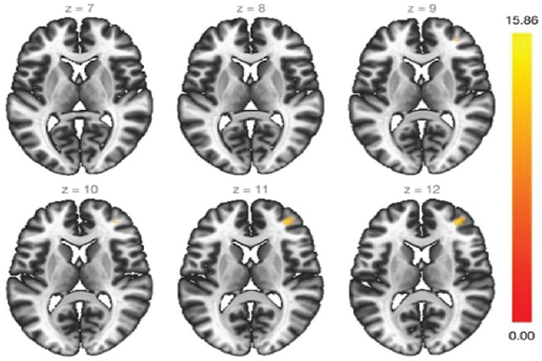

При оценке 1-го и 2-го кластеров сенсомоторной нейросети отмечается увеличение функциональной коннективности в области лобных долей (рис. 4, 5).

Рис. 4. Кластер № 1 сенсомоторной нейросети

Fig. 4. Cluster N 1 of the sensorimotor neural network

Рис. 5. Кластер № 2 сенсомоторной нейросети

Fig. 5. Cluster N 2 of the sensorimotor neural network

Обнаружено повышение функциональной коннективности в левой височной доле (рис. 6), особое внимание обращает на себя тот факт, что изменение функциональной коннективности происходит в сером веществе и площадь увеличения активности довольно большая.

Рис. 6. Кластер № 3 сенсомоторной нейросети

Fig. 6. Cluster N 3 of the sensorimotor neural network

При оценке кластера № 4 (рис. 7) отмечается увеличение функциональной коннективности в угловой извилине. Угловая извилина — регион головного мозга, лежащий в основном в антеролатеральном регионе теменной доли. Ее значение связано с передачей визуальной информации в область Вернике для усвоения письменной речи.

Рис. 7. Кластер № 4 сенсомоторной нейросети

Fig. 7. Cluster N 4 of the sensorimotor neural network

Сенсомоторная нейросеть также показала положительный прирост функциональной коннективности как в областях собственных структур, так и в области лобных долей и височной доли слева (все пациенты — правши), что позволяет предположить, что у пациентов повышается контроль за собственными движениями и восстанавливаются области, которые ответственны за получение двигательных навыков.